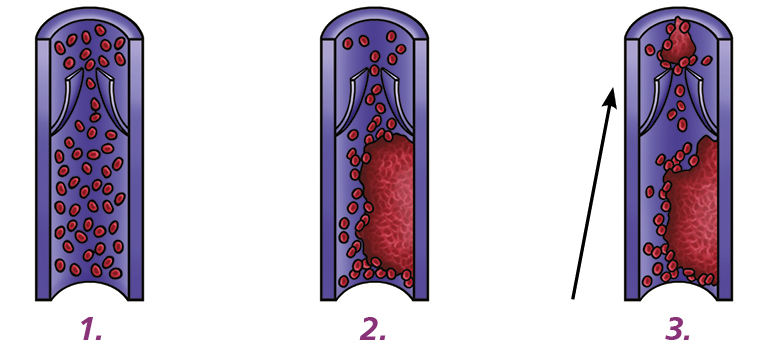

Deep Vein Thrombosis (DVT): a DVT is a blood clot that forms in a deep vein, most commonly in your leg or pelvis.

Pulmonary Embolism (PE): if all or part of the DVT breaks free and passes through your blood vessels, it can reach your lungs. This is called a PE.

Yes. ‘DVT’s are serious because they can result in long term complications such as permanently swollen/discoloured legs, varicose veins, and leg ulcers (known as post thrombotic syndrome).

Also part or all the DVT can break off. If this happens it will travel through your blood vessels and can reach your lungs, this is known as a PE. This is potentially life threatening. Prompt treatment saves lives. While dying from a PE is very rare it remains one of the commonest causes of death in pregnancy in the U.K.